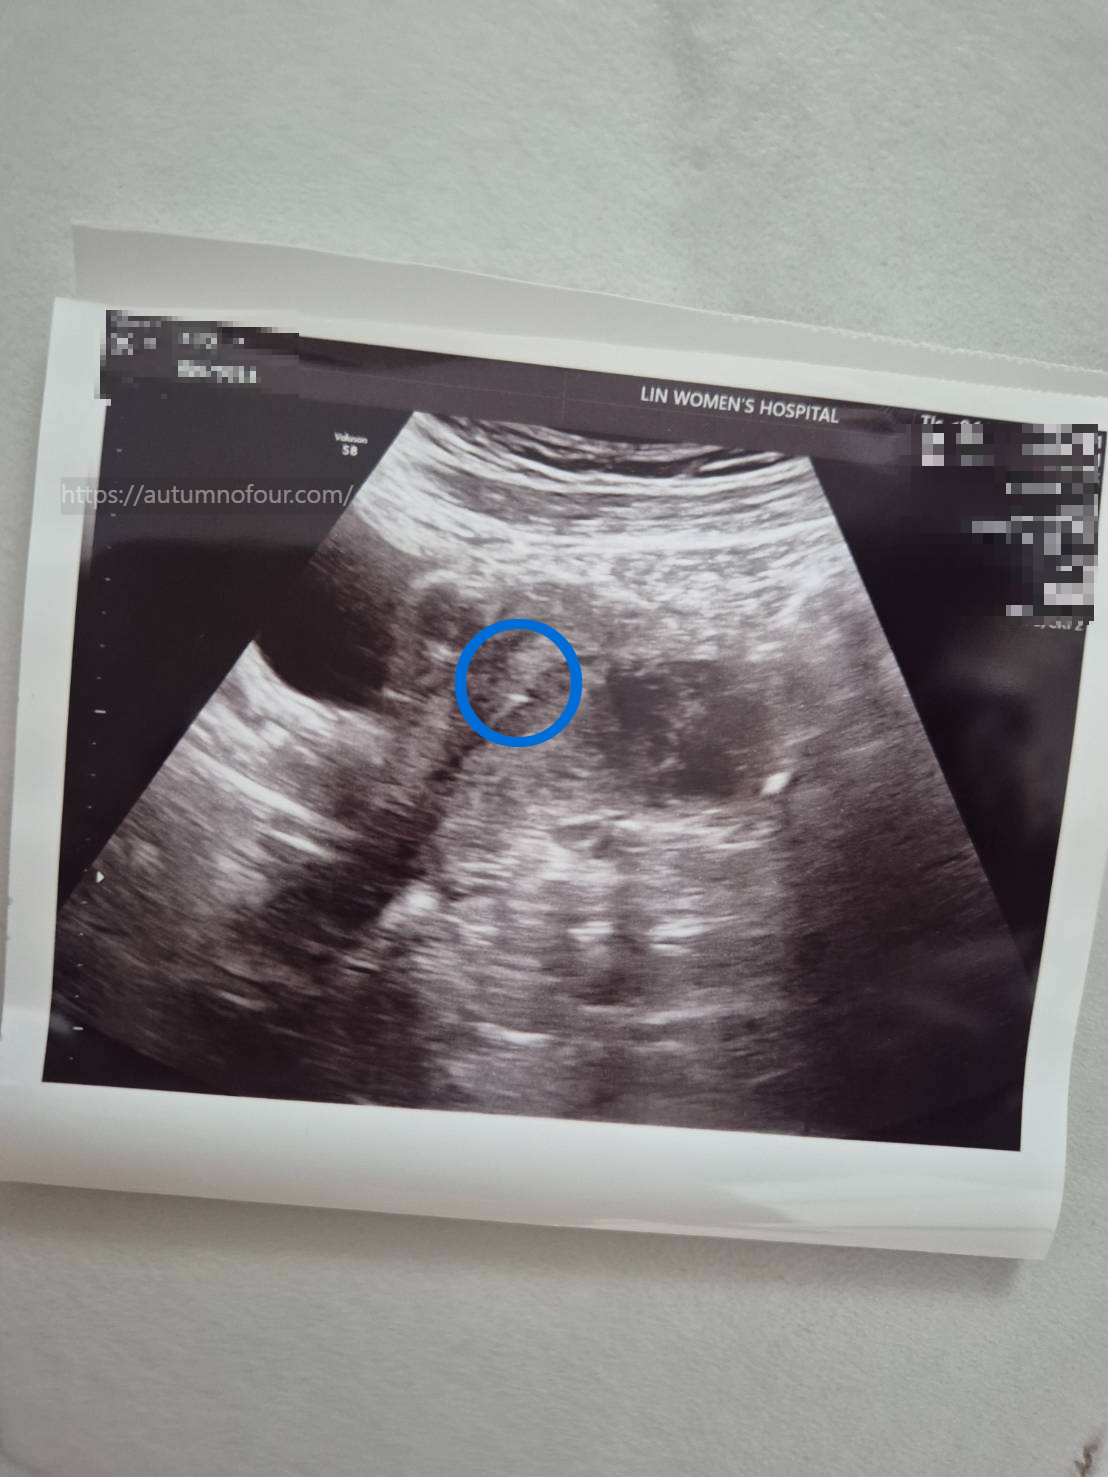

이식될 배아의 사진을 보여주신 후 (나중에 보니 핸드폰으로도 사진을 찍어주셨다) 본격적인(?) 이식을 시작했다.

오늘 이식할 우리의 배아! 무려 5일 1등급 짜리, 두둥

난 누워있어서 보지 못하지만, 이식 과정 하나하나 간호사분께서 계속해서 얘기해주셨는데,

배초음파로 보면서 이식을 하는게 신기했다.